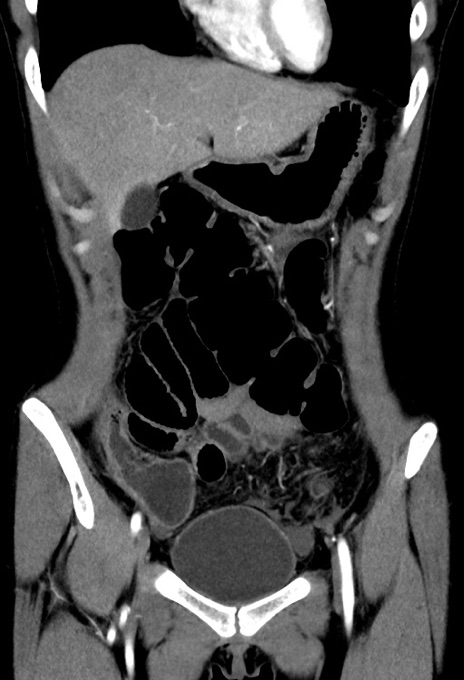

横断像

【症例】20歳代女性

【主訴】嘔吐、下腹部痛

【現病歴】昨日夕食後に嘔吐し下腹部痛が出現。本日になっても嘔吐持続し改善しないため来院。

【身体所見】意識清明、BT 37.2℃、BP 108/67mmHg、腹部:平坦、やや硬、下腹部正中から右にかけて圧痛あり、反跳痛軽度あり、tapping pain(+)。

【データ】WBC 13600、CRP 14.94